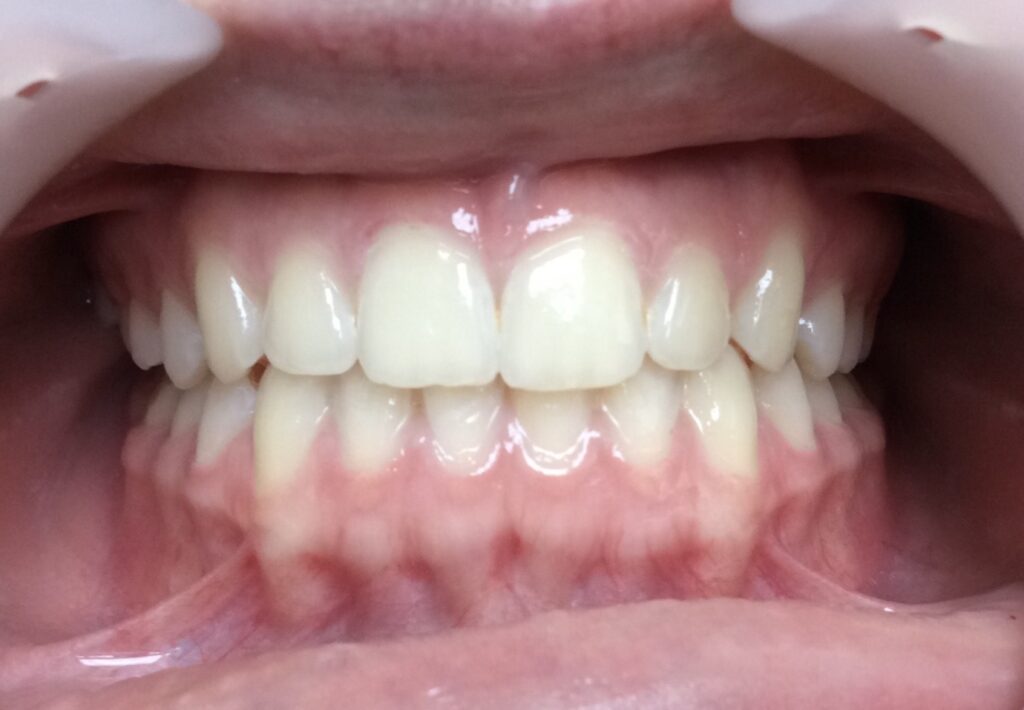

Un cas de recouvrement trop important avec bruxisme sévère :

La photo intermédiaire permet de voir que la situation en denture mixte était bien plus favorable qu’au départ. Quelle dentition aurait eu ce patient si on l’avait traité seulement à 12 ans ? et toutes les tensions dans son corps qui accompagnent ce genre de cas auraient surement perturbé sa croissance générale.

Photos à 6 ans, 9 ans et 15 ans